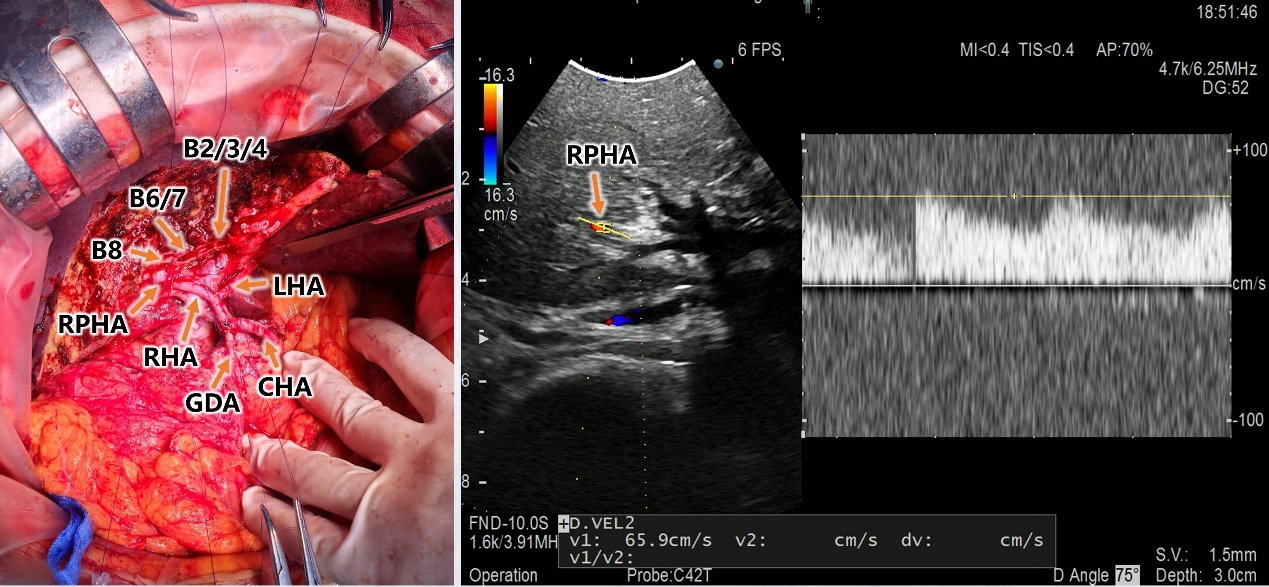

手术中最关键、最富挑战性的环节在于肝动脉的切除与重建。术中,主刀医生需要将直径不足 3 毫米的右肝动脉主干与直径更是不足 2 毫米的肝右后动脉进行端端吻合。这要求手术团队具备高超的显微外科技术和稳定的心理素质。最终,团队凭借在血管精细解剖与吻合方面积累的深厚功底,成功完成了毫米级的动脉吻合重建。术中超声实时监测确认血流畅通无阻(对应图 4),术后增强 CT 也再次证实了重建动脉的通畅,肝脏血供良好,未见缺血表现(对应图 5)。